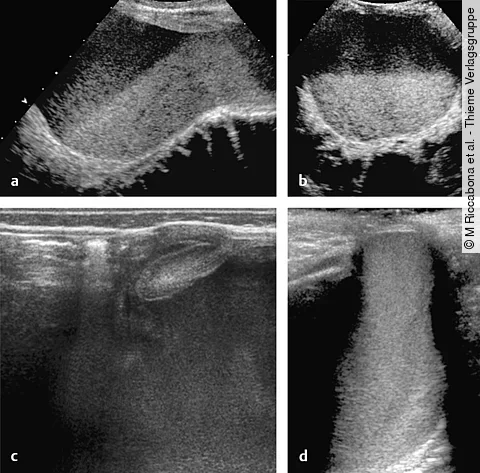

Ultraschallbild